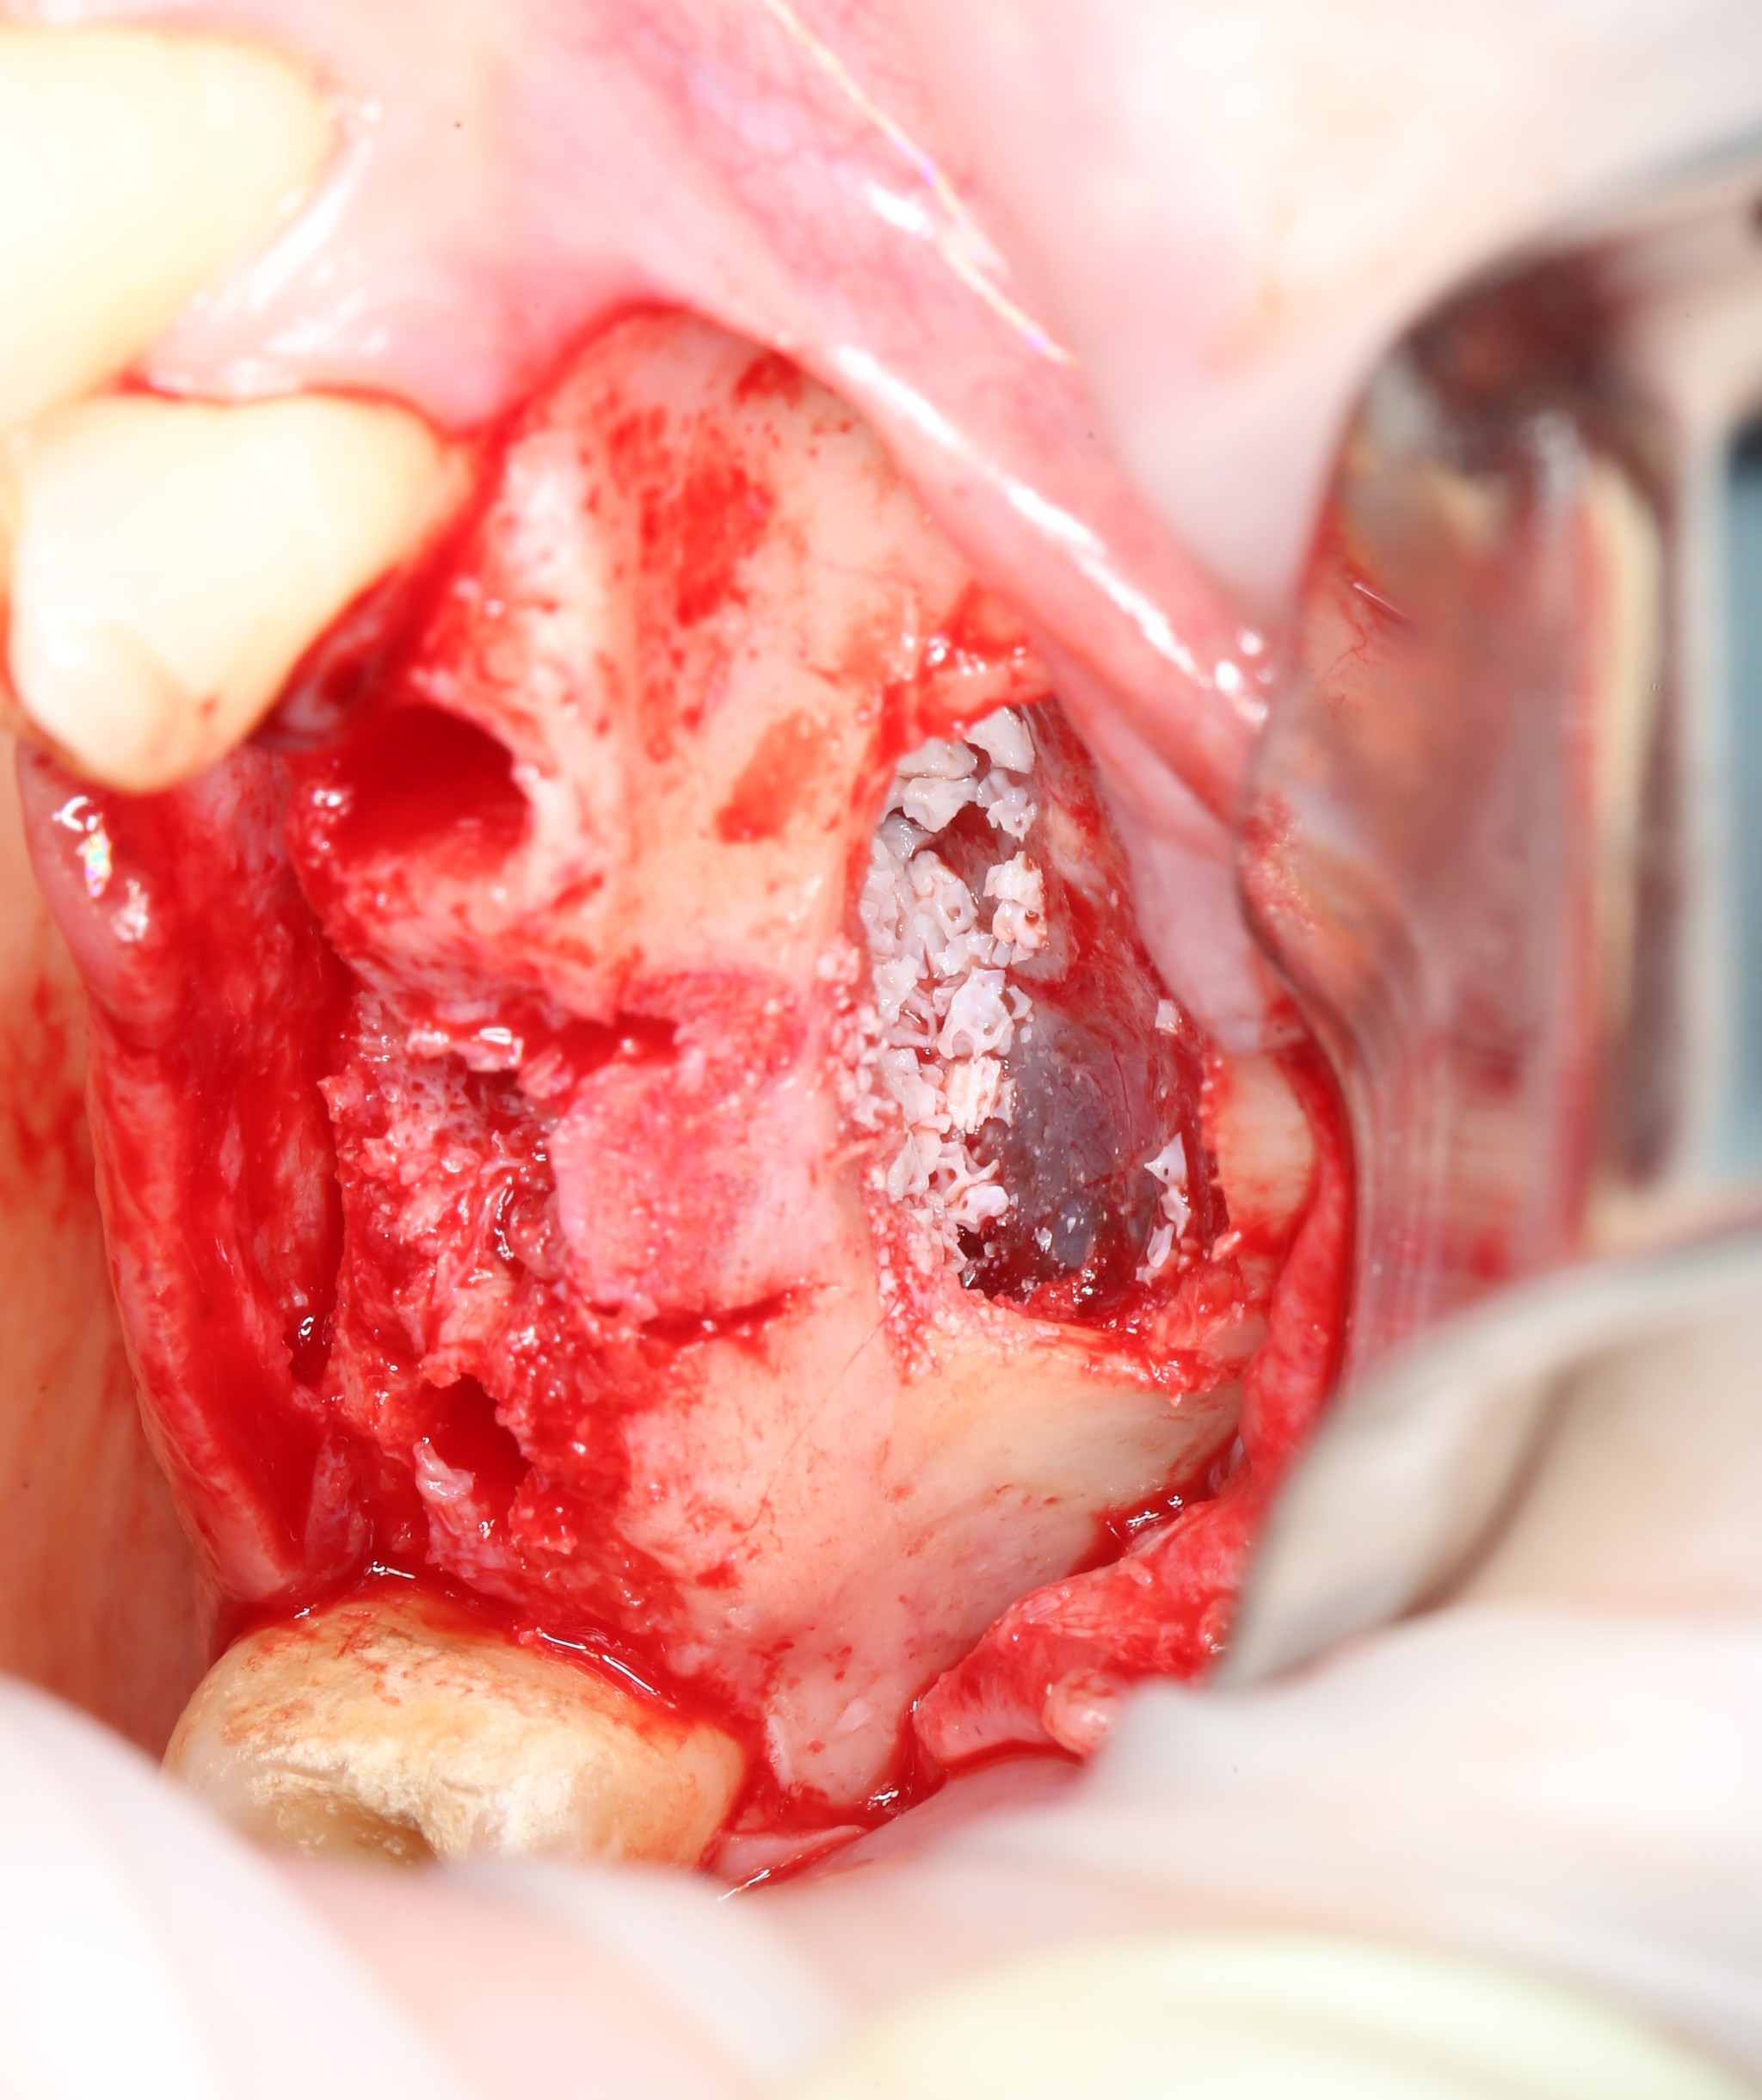

Производится внесение костного материала.

Так это выглядит в полости рта:

Костный материал распределяется порционно:

Со стороны сформированных лунок можно проконтролировать его распределение:

Четко видно, что костная стружка уложена именно там, где будут располагаться имплантаты.